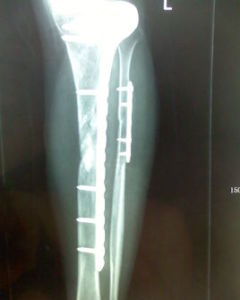

股骨頭壞死的手術治療植骨術:骨移植可刺激股骨頭內血管再生,促進修復和癒合,同時防止股骨頭塌陷,適用於年輕的股骨頭壞死ⅱ期和期股骨頭壞死ⅲ期的股骨頭壞死患者,可延緩病程發展和全髖置換的時間。若結合生長因子或電刺激等促進骨折癒合的方法,可望提高療效。對於鑽孔減壓效果較好的早期股骨頭壞死患者,亦可考慮同時植骨。